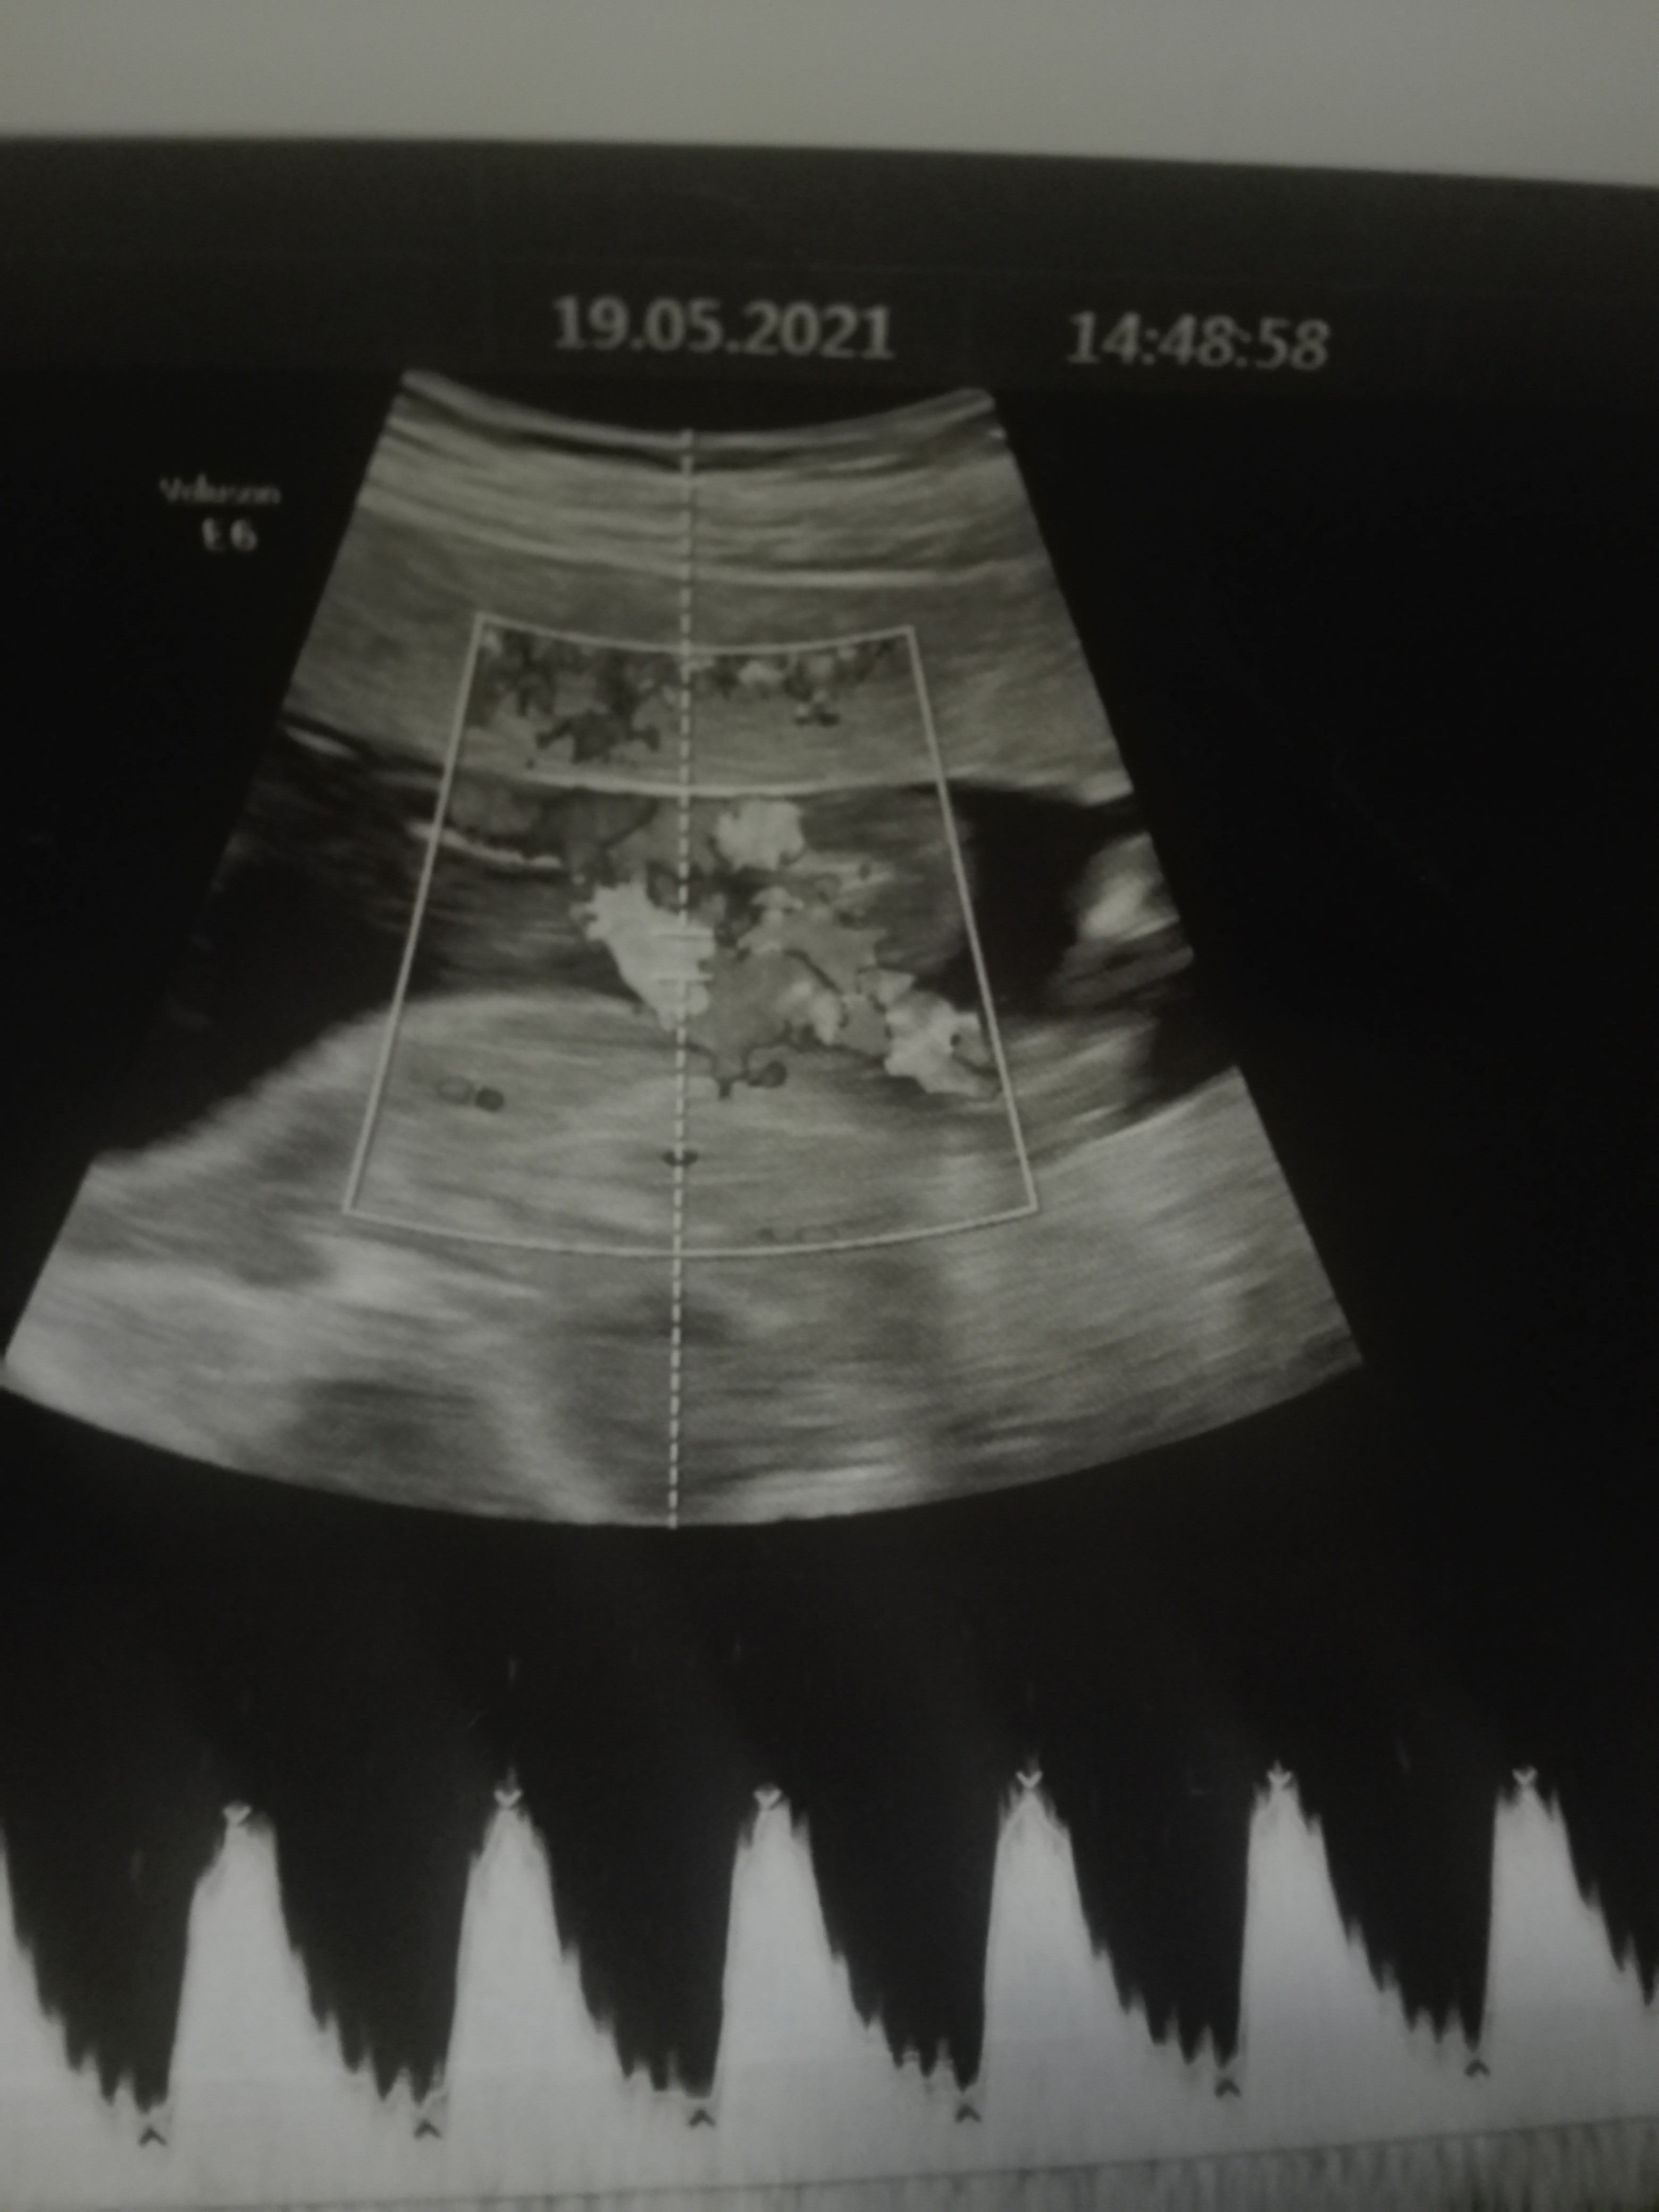

I co ? chłopczyk ?Witam, czy na podstawie tych zdjęć usg można rozpoznać płeć?

jestem tu nowa i dopiero poznaję forum. Nie wiem, czy w dobrym miejscu to zamieszczam, ale czy coś z tego USG widać co do płci?

Hej,